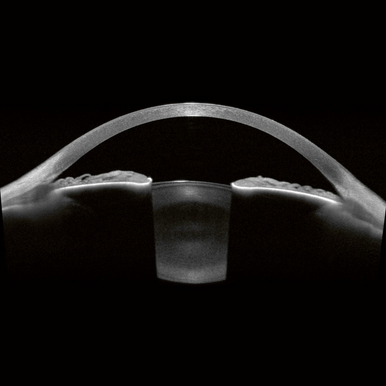

En tant que base de la plateforme ANTERION, l’App Imaging se concentre sur la visualisation haute résolution de l’ensemble du segment antérieur, de la surface antérieure de la cornée à la surface postérieure du cristallin. Elle fournit des images OCT à source balayée impressionnantes et révélatrices qui apportent une confirmation visuelle et ajoutent de la fiabilité et de la précision au diagnostic et au suivi des altérations du segment antérieur.

L’application Cataract de l’ANTERION combine des mesures clés pour la planification de la chirurgie de la cataracte : l’analyse de la cornée, la profondeur de la chambre antérieure, l’épaisseur du cristallin et la longueur axiale. La technologie optimisée de l’OCT à source balayée permet des mesures précises et une confirmation visuelle en fournissant des images haute résolution, même à travers des cataractes denses.

L’application Metrics de l’ANTERION présente des images OCT à source balayée d’une clarté exceptionnelle avec la chambre antérieure affichée en vue radiale.

Les images OCT haute résolution constituent la base idéale pour des mesures précises. Déterminez les paramètres d’angle prédéfinis ou effectuez des mesures à main levée adaptées à chaque cas clinique. Outre les paramètres couramment utilisés, l’application Metrics propose la mesure de la profondeur de la chambre antérieure, ainsi que de l’épaisseur et la courbure du cristallin.